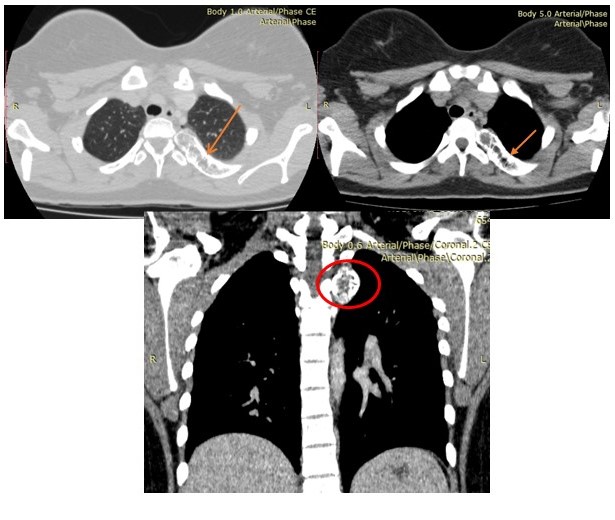

En la TC de tórax con reconstrucción en 3D, se evidenció imagen hiperdensa con áreas hipodensas en su interior, redondeada de bordes bien definidos microlobulados que mide 4,3 cm x 4,3 cm a nivel del 1/3 proximal del décimo (10o) arco costal posterior izquierdo con protrusión de dicha lesión hacia parénquima pulmonar y partes blandas dorsal compatible con lesión neoplásica benigna. Resto del plano óseo y blando sin evidencia de lesiones (Figura 8).